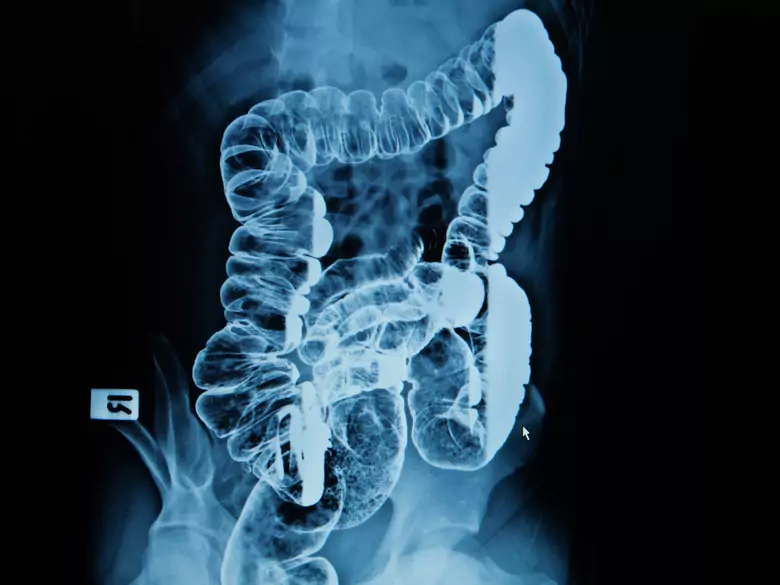

Intestins